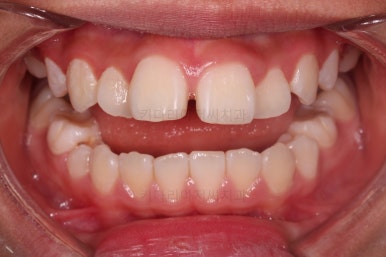

전후 비교해 볼게요.

웃을 때 보이는 느낌도 많이 좋아졌고요.

옆에서 웃는 모습을 보면 윗니도 들어간 모습이 보이죠.

물론 아직 약간의 돌출감이 있긴하지만 아이 기준으로는 나쁘지 않고, 특유의 두툼한 입술을 가진 환자분이라면 무조건 입이 많이 들어간다고 답은 아닙니다.

정교한 조절은 안했지만 치열이나 교합/맞물림 등 매우 좋아졌습니다.